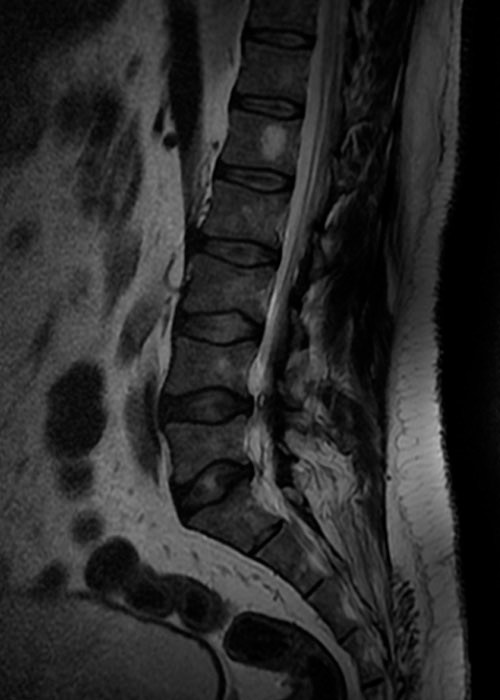

Tras la observación del caso, diagnosticamos una estenosis de canal central L4L5 con signos de compresión radicular en el territorio de L4L5 y L5S1 lo que provocaba una claudicación neurógena y le estaba impidiendo andar con normalidad.

Con la realización de una resonancia magnética observamos además una severa degeneración del disco mencionado y una hipertrofia facetaria acompañando a la estenosis de canal detectada anteriormente.